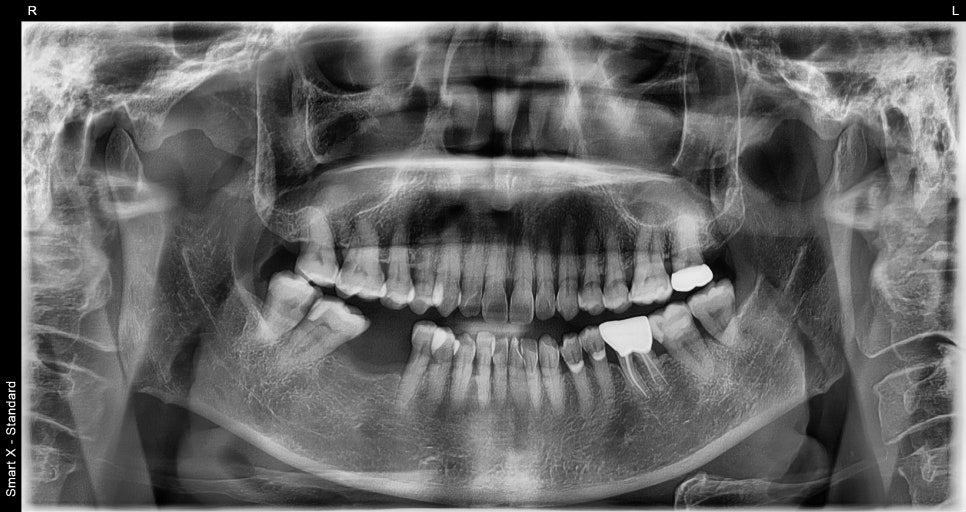

Initial X-ray at the first visit

She visited us saying, “The molar space where I had a tooth extracted before has been bothering me more lately, and I can’t chew food well.”

A foreign woman in her 50s came to the clinic,

and the panoramic X-ray showed that the first molar on the lower right had been left in an extracted state, with the adjacent teeth beginning to tilt slightly.